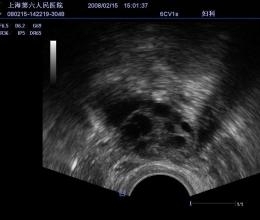

- Поддержка различных типов датчиков, включая линейные, конвексные и внутриполостные, что расширяет возможности диагностики;

- NGB-004 — многоразовая (металлическая) биопсийная насадка для датчиков 6CV1s, V10-4s, V10-4Bs;

- Режимы сканирования: B/M/Color Doppler/Color M/Power/Directional Power Doppler Flow Imaging;

- Shared Service Package — предустановленные параметры, аннотации, маркеры и программы измерений для абдоминальных исследований, акушерства, гинекологии, кардиологии, ангиологии, малых органов, урологии, педиатрии, неотложной медицины;

- DICOM Ob/Gyn S/R — структурированный отчёт по акушерству и гинекологии;